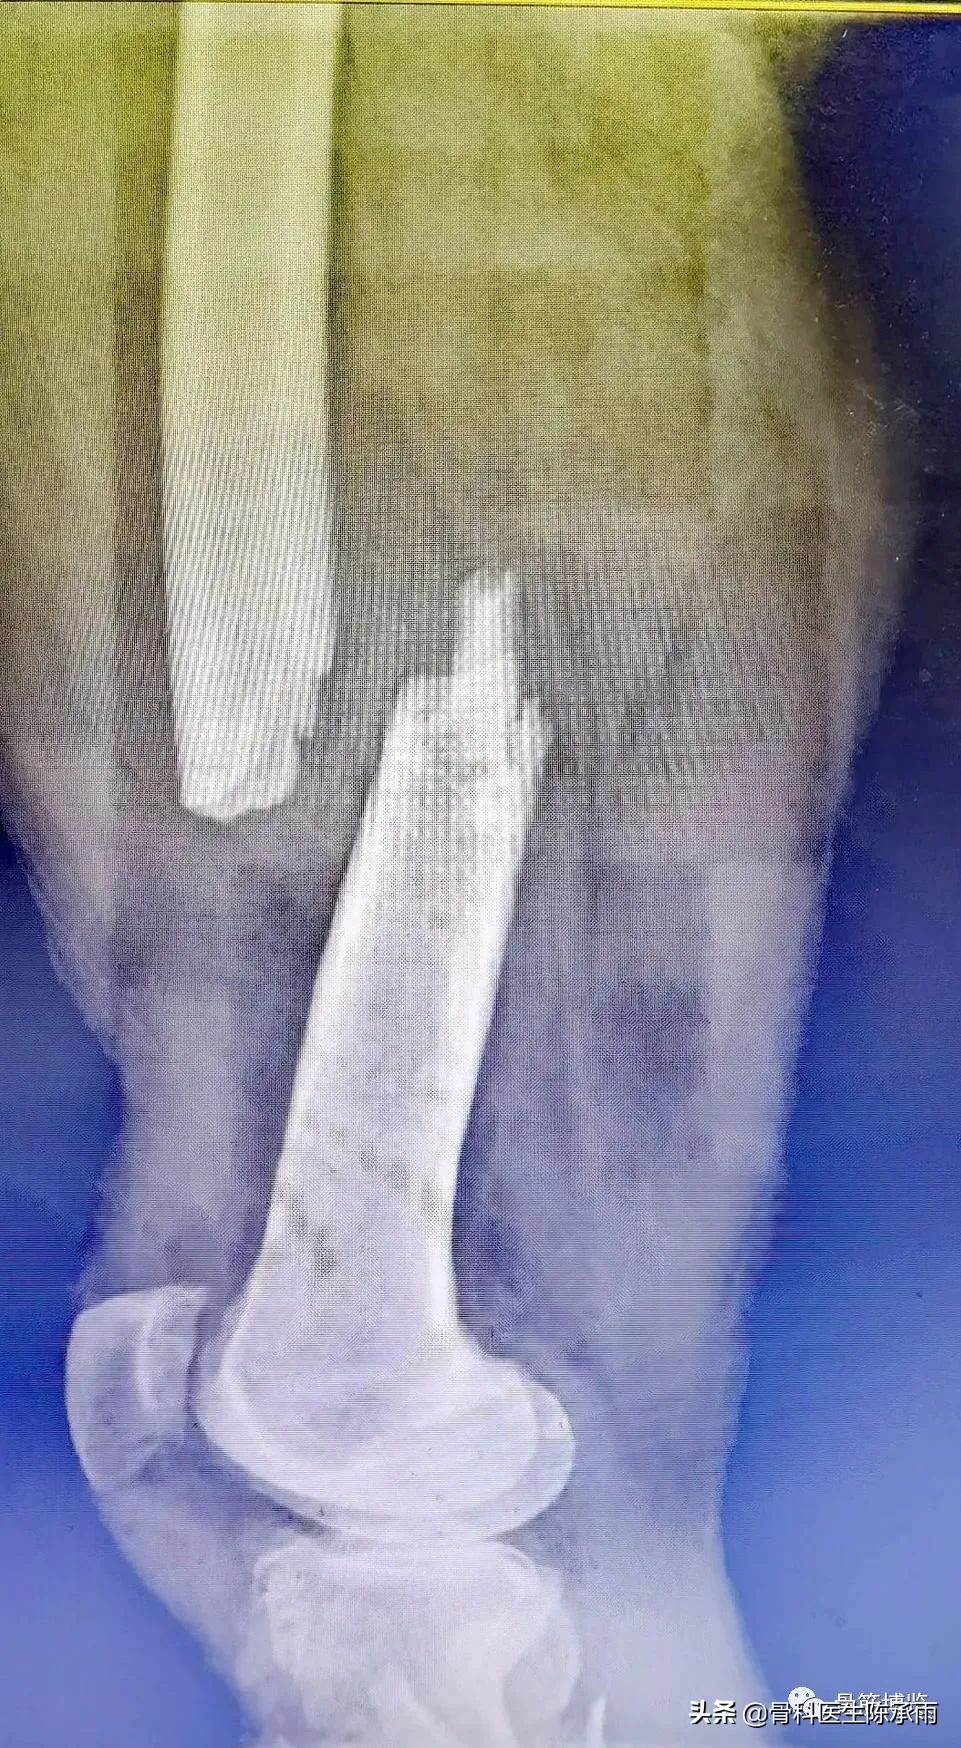

这2例患者皮肤条件差,全身多发骨折,小腿皮肤条件差,1例筋膜高压切开,1例整个小腿布满张力性水泡,胫骨骨折都在伤后30天才能手术。